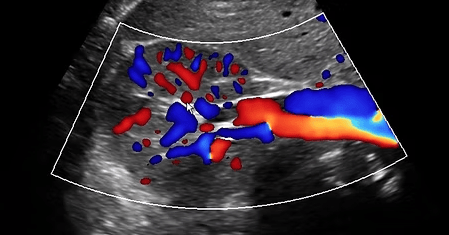

Abdominal Aortic Aneurysm

The aorta and its branches take the blood from the heart down to the abdomen and legs. We can assess for dilatation of the arteries called an aneurysm which often have no symptoms and plaque build up causing narrowing of the artery.

Renal Doppler

A renal Doppler ultrasound is performed to assess the blood flow in the renal arteries, which supply blood to the kidneys. It helps identify any blockages or narrowing of these arteries, which can lead to conditions like renal artery stenosis or high blood pressure.